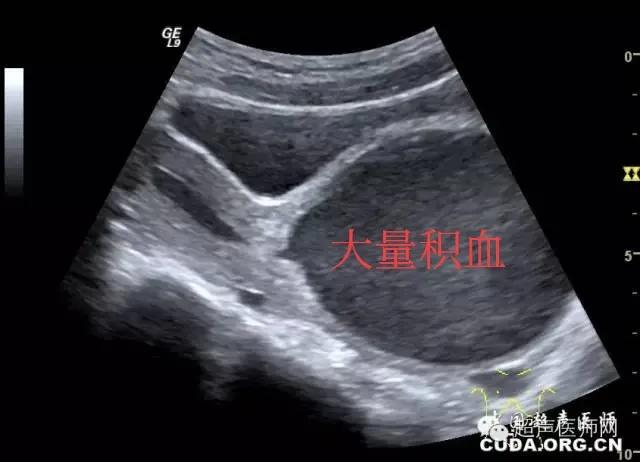

一个小时左右,小姑娘的妈妈那些单子回来了,彩超示:有YD扩张积液,宫腔扩张,呈“哑铃”状。现在谜底终于解开了,造成尿潴留的原因就是“chu女膜闭锁”,也就是有时候人们常说的 “石女” !

“大姨妈”出不来老是积在YD里,血液可经过输卵管流到肚子里面,反复多次的“大姨妈”会使积血越来越多,可造成子宫腔、输卵管、盆腔的积血,输卵管可因为积血而造成粘连导致输卵管伞端闭锁,积血流到盆腔引起子宫内膜异位症,甚至会引起不孕。

这个小女孩住院后行了手术治疗,切开闭锁的膜后放出了大约500ml的积血,术后5天康复出院。 看着小姑娘出院时高兴的表情,我也开心的笑了!